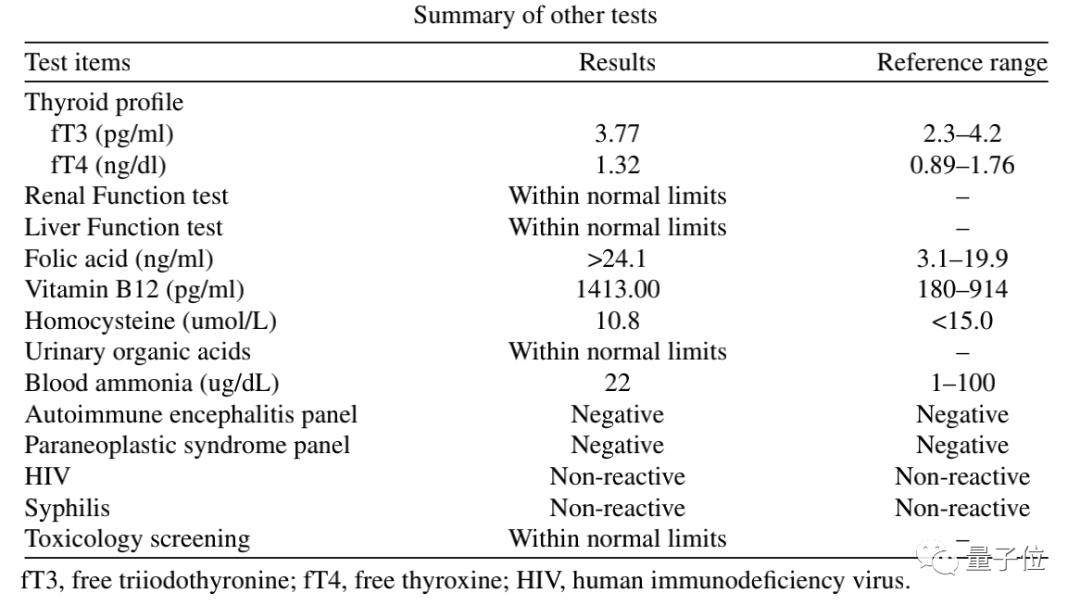

而且他的免疫系统正常,也并未出现感染和心理问题。